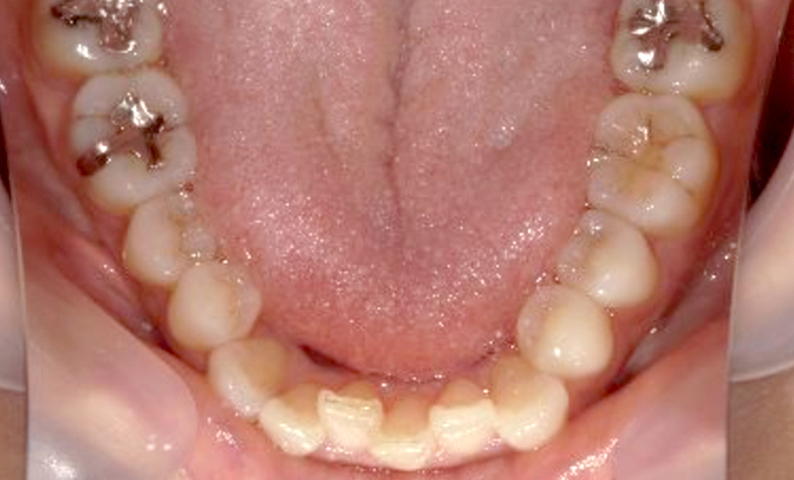

症例_003 下顎だけの部分矯正

治療期間:10ヶ月金額:24万円+税女性前歯のガタガタ下の前歯だけ上顎は補綴治療中

| Before | After |